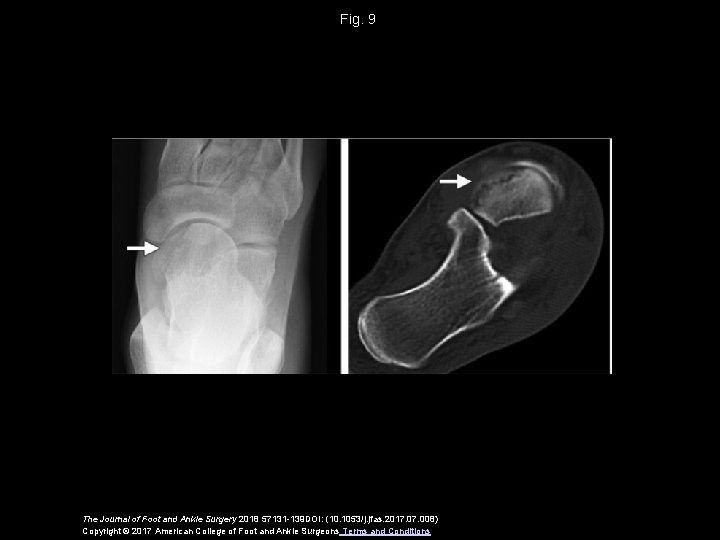

Fig. 9 The Journal of Foot and Ankle Surgery 2018 57131 -139 DOI: (10. 1053/j. jfas. 2017. 008) Copyright © 2017 American College of Foot and Ankle Surgeons Terms and Conditions